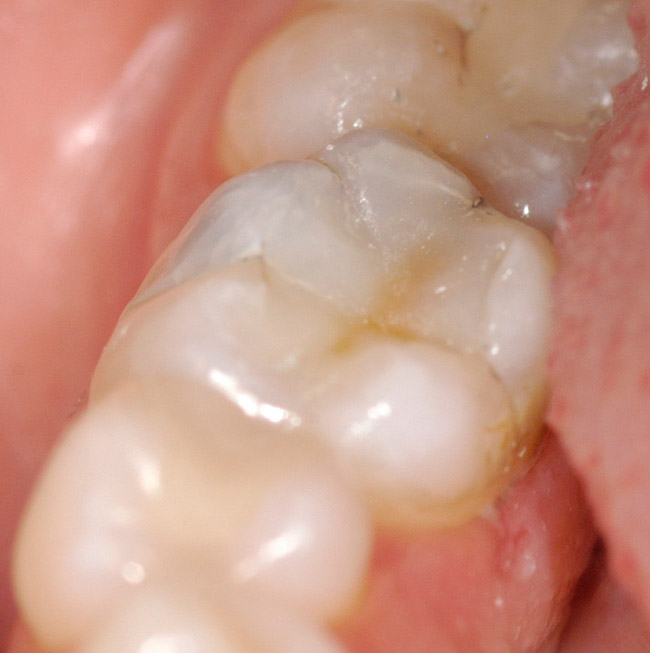

Figure 7   The final restoration ready for years of service.

Figure 7

The enamel layer is shaped using composite hand instruments and is photopolymerized (Figure 6). The occlusion may now be checked using a marking paper and adjusted using smooth diamonds and multifluted carbide burs. After the occlusion has been adjusted and no interferences remain, the final restoration may be polished (Figure 7).